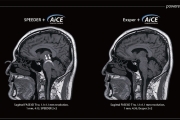

Az AiCE és a PIQE Deep Learning technikákat alkalmaz a zaj eltávolítására és az SNR növelésére, hogy tiszta, éles és jól elkülöníthető képeket kapjunk.

Az új technikák, például a Deep Learning rekonstrukciós technológia a felbontás, a sebesség és az SNR közötti kompromisszumok összehangolásával fejlesztik az orvosi képalkotást. Emellett a gyorsított szkennelési technikák, a számszerűsíthető képalkotás, valamint a torzítás és a műtárgyak csökkentésére szolgáló módszerek fokozzák a diagnosztikai képességeket.

PIQE képalkotás elérése az MRI számára

A Precise IQ Engine (PIQE) a Canon Medical nagy felbontású mélytanulásos rekonstrukciója az MRI-hez. A PIQE növeli a mátrix méretét, eltávolítja a zajt, és éles anatómiai képeket biztosít, hogy az MR-képalkotást a következő szintre emelje.